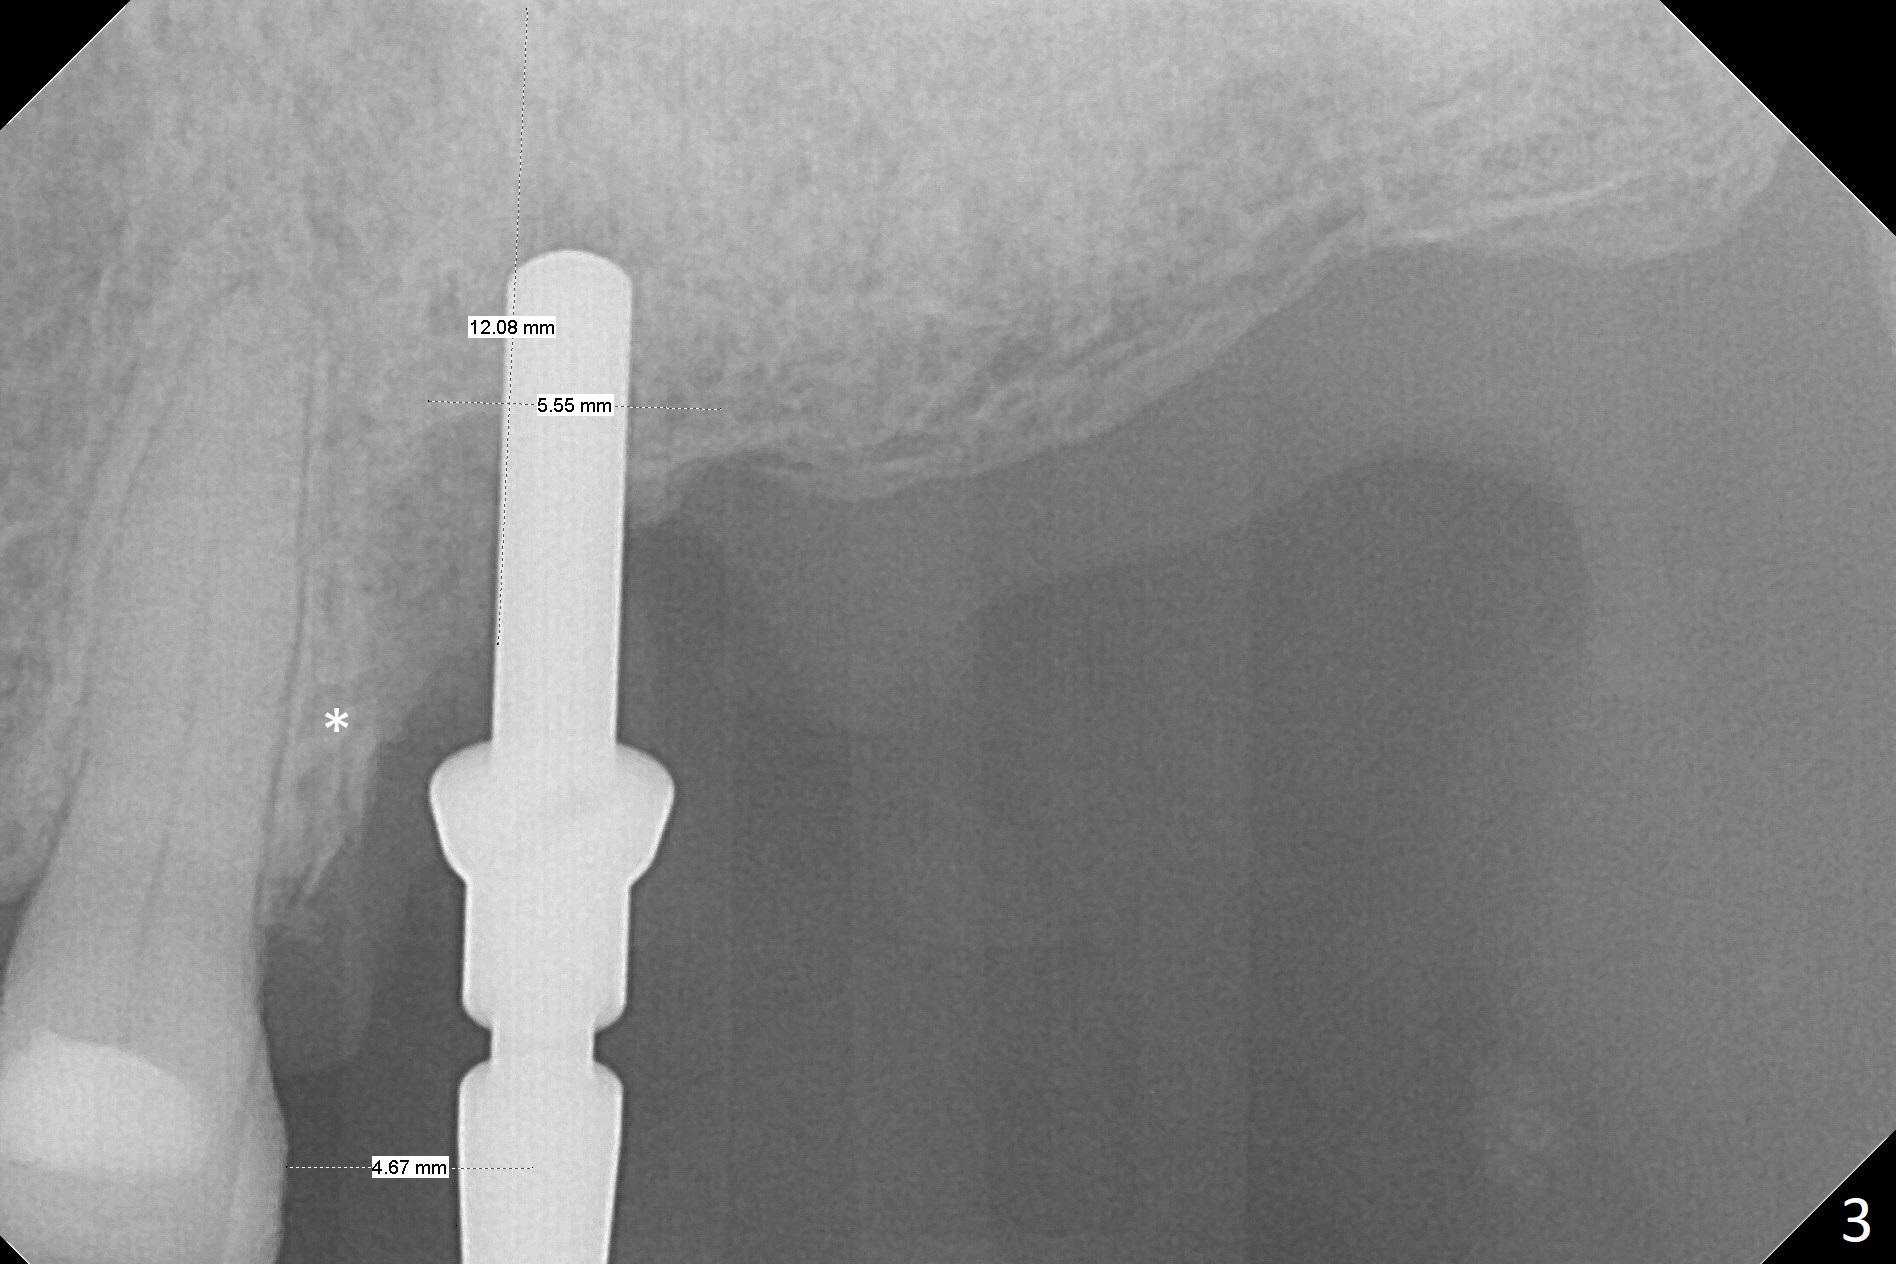

The septum is found to be pointed after extraction of the tooth #14 (Fig.1 *). The septum is flattened with Rongeur (Fig.2 *) prior to osteotomy. Because of interference of the mesial bone (Fig.3 *), osteotomy does not reach the depth with use of stopper. Without the latter, a 5x11.5 mm implant barely penetrates the sinus floor (Fig.4 (no postop nasal hemorrhage)). Also due to the mesial bone interference, a 6.5 mm abutment is not seated. Finally a 5.5x7(5) mm abutment is placed for an immediate provisional. Periodontal dressing is applied to cover the buccal repaired gingiva (Fig.5 *). There is minimal thread exposure after removal of the provisional nearly 2 months postop (Fig.6). The provisional does not return for easy self cleansing. In fact this is not an easy task, because of the posterior position (Fig.8 (after Piezo scaling)). The distal implant remains exposed; the abutment is removed and a healing screw is placed (Fig.9). The implant should have been subcrestal distally (Fig.7 <, nearly 3 months postop). One month later, the implant seems to be buried (Fig.10). The straight abutment is changed to an angled one (4.5 x15 degree A (5) mm) before impression retake (Fig.11,12 (<, dashed line: access hole)). The implant should have been placed more mesial (Fig.13). Surgical guide is needed. There is no implant exposure clinically or in CBCT sections 1 year 2 months post cementaton (Fig.14), although 3 D image suggests missing distopalatal plate (Fig.15).